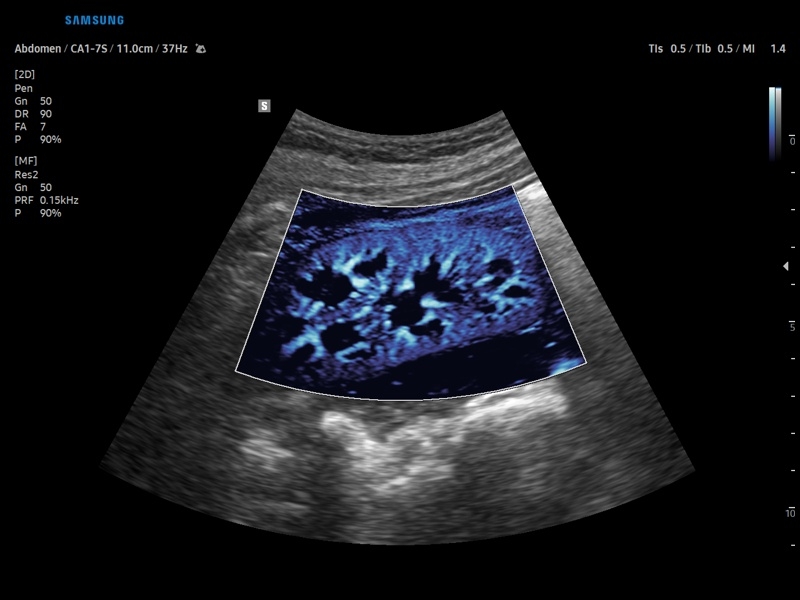

• Абдоминальные исследования

• Модуль CEUS+ (Contrast Enchansment UltraSound) - программа, позволяющая проводить обследование с применением контрастных агентов.

• Модуль MV-Flow – программа (режим), позволяющая визуализировать кровоток в микроциркуляторном русле с высоким разрешением без использования контраста.

• Модуль LumiFlow – программа отображения кровотока с объемной графикой для лучшего понимания архитектоники сосудистого русла.

• Технологии визуализации: MV Flow, LumiFlow, SEE Stream, Panoramic

• 3D - трехмерное сканирование объемными датчиками в статическом режиме в серой шкале и восстановление объемной структуры сосудов в режиме цветного / энергетического допплера (необходим Static 3D).